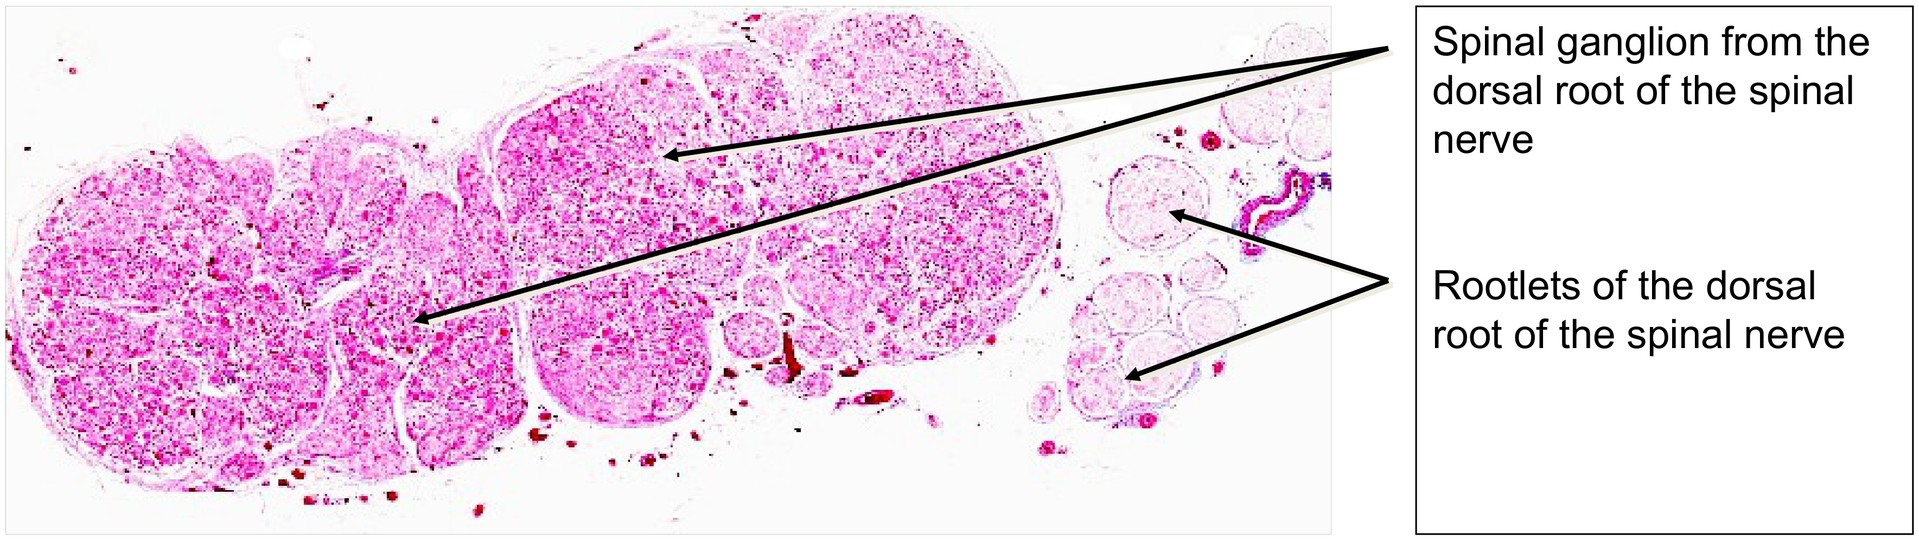

To understand the structure of a spinal ganglion, including its pseudo-unipolar neurons and the rootlets of the dorsal root of a spinal nerve.

The spinal ganglion (sensory ganglion) lies at the junction between the peripheral nervous system (PNS) and the central nervous system (CNS). It forms part of the dorsal root of the spinal nerve. Alongside the dorsal root ganglion, the afferent (sensory) fibers of the spinal nerve enter the spinal cord. The ventral root, in contrast, contains only efferent (motor) fibers, some of which can also be observed in this specimen.

A large proportion of the neuronal nuclei are located towards the periphery of the ganglion. The neurons are pseudo-unipolar, meaning that a single process leaves the perikaryon, dividing shortly afterwards into an axonal (neuritic) and a dendritic branch. The dendritic process conducts impulses from peripheral sensory receptors (e.g. tactile corpuscles in the skin), while the neuritic process continues centrally towards the spinal cord, where it forms synapses.

Each ganglion cell is surrounded by a layer of satellite cells, which may appear separated by small gaps — artefacts created during tissue fixation. Between the ganglion cells, particularly in the central area of the ganglion, afferent nerve fibers can be seen, though their sheaths (such as myelin) are often poorly preserved. After fixation, remnants of the Schwann cell sheaths appear as “neurokeratin”, a term unrelated to true keratin.

• Orient yourself using the overview and determine which structures belong to the dorsal root and which to the ventral root of the spinal nerve.

• Locate the spinal ganglion within the dorsal root and compare the sizes of the ganglion cells.